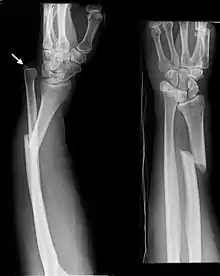

Fractures of the ulna can occur at different levels of the bone: near the wrist, in the middle or near the elbow.[2] The fracture may be confined to the ulna or accompanied with damage to the radius or the wrist or elbow joints.[2]

- Nightstick fracture is a fracture of the middle portion of the ulna without other fractures.[1]

- Distal ulna fractures typically occur along with distal radius fractures.[3]

- Monteggia fracture - a fracture of the near to elbow end of the ulna with the dislocation of the head of the radius at the elbow joint.[2]

- Galeazzi fracture - not a fracture of the ulna but a displaced fracture of the radius accompanied by a dislocation of the ulna at the wrist, where the radius and ulna come together.[2]

Monteggia Fracture (fracture of proximal ulna)

Galeazzi facture (displaced fracture of the radius)